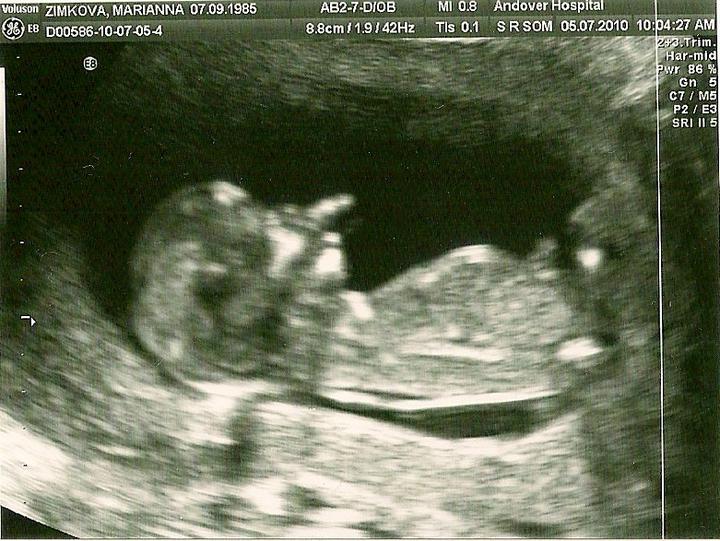

mam dve lasky pri sebe jednu v brusku a druhu na kolienku co mi moze viac xybat ? 🙂

od zajtra mame 50dni a potom uz to bude blizsie a blizsie k nasej malickej tesim sa 🙂

jejda malicka sa uz zobudila a kopka o dusu ..... 🙂